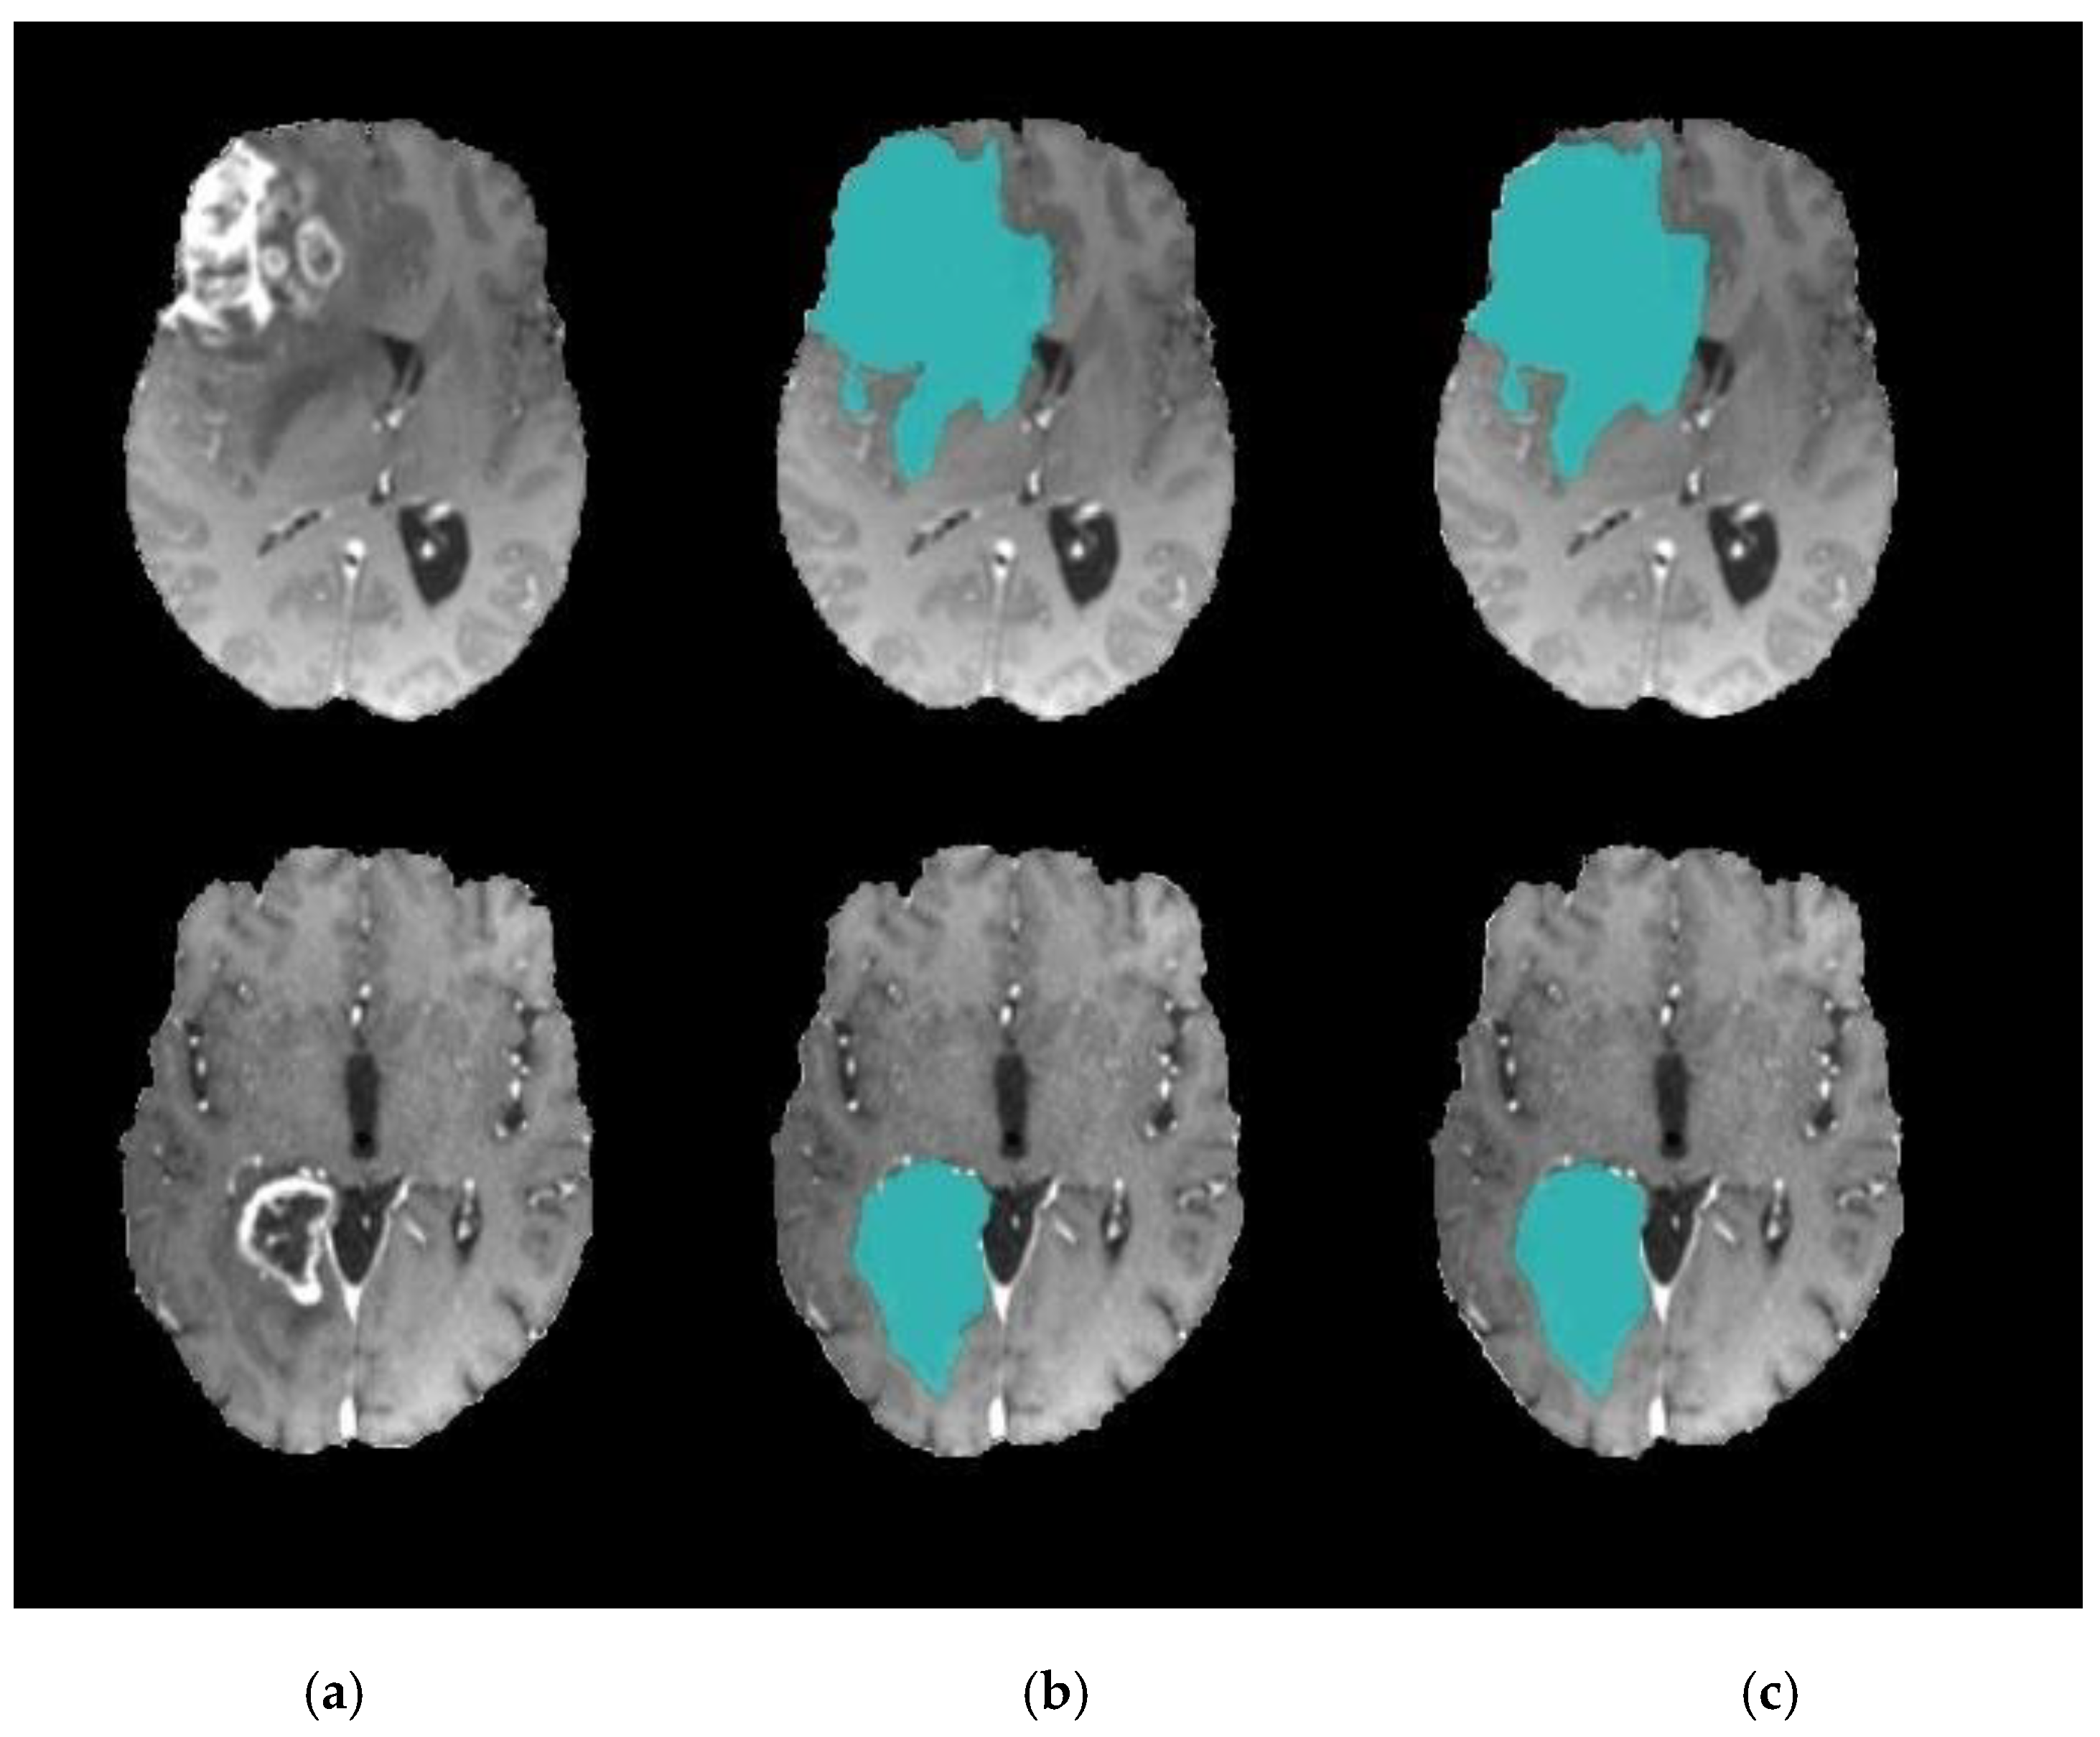

The results confirm the superiority of the suggested model as it increases the accuracy by 5.27% compared with the SVM-based brain segmentation algorithm. One possible explanation of this result is that using a two-step DA approach enhances segmentation accuracy as it detects an accurate initial contour rather than choosing it randomly or less accurately, as is done in the compared methods. The search mechanism of DA is maintained by the utilization of the information obtained from k-means. In other words, the connection between k-means and DA helps to increase accuracy and decrease the error rate. Figure 8 shows a sample of segmentation results.

Figure 8.

Brain tumor segmentation (a) 2D slice (b) final segmentation using DA.